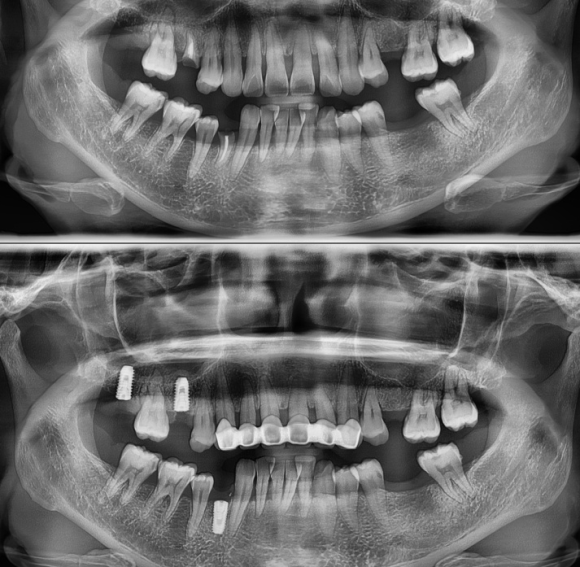

상기 환자 치아를 살릴 수 없을 만큼 치아가 파절되어 내원하였습니다.

임플란트 총 5개를 계획하였으며,

3개 발치 후 즉시 임플란트 식립을 진행하였습니다.

난발치 후 즉시 임플란트 2개 and simyltaneously lifted along with fixture insertion.

매우 복잡한 술식이 따랐습니다.

총 수술시간은 15분 이었습니다.